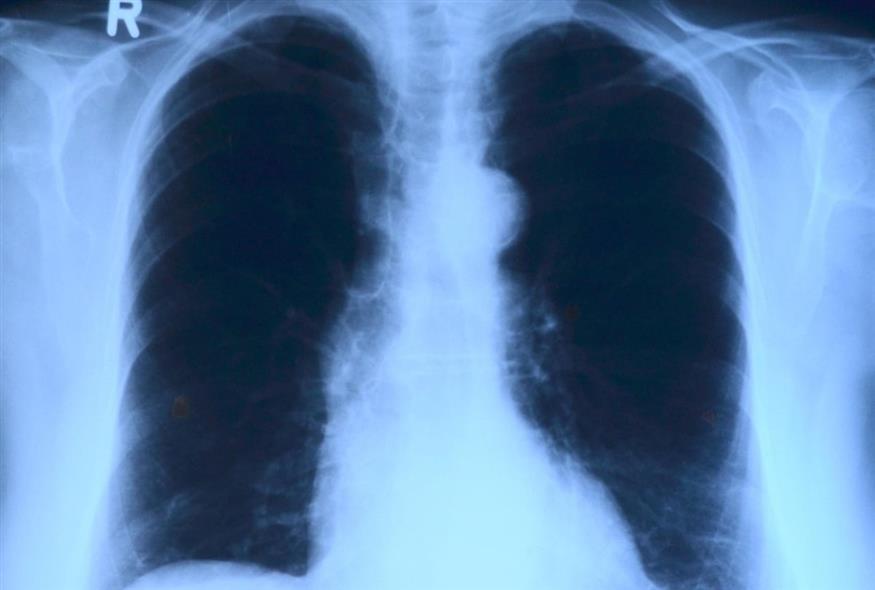

Οι πνεύμονές μας είναι ζωτικής σημασίας για κάθε αναπνοή που παίρνουμε. Τώρα, μια ερευνητική ομάδα βρήκε έναν τρόπο ώστε η τεχνολογία να μιμείται πλήρως τις σύνθετες λειτουργίες των πνευμόνων ενός ατόμου, τουλάχιστον για λίγο χρονικό διάστημα.

Στην προκειμένη περίπτωση, όμως, δεν υπήρχε χρόνος. Ο ασθενής, ένας 33χρονος άνδρας, νόσησε σοβαρά από γρίπη η οποία οδήγησε σε οξεία αναπνευστική δυσχέρεια (ARDS), μια απειλητική για τη ζωή κατάσταση με διαρροή υγρών στους πνεύμονες. Επιπλέον, νόσησε με βακτηριακή πνευμονία και οι πνεύμονές του, μαζί με τα νεφρά και την καρδιά του, άρχισαν να παρουσιάζουν ανεπάρκεια. Η μόνη του ελπίδα ήταν διπλή μεταμόσχευση πνευμόνων, αλλά οι γιατροί φοβούνταν ότι το σώμα του θα ήταν πολύ αδύναμο για να αντέξει τη διαδικασία, ενώ η προσπάθεια να κρατηθούν οι πνεύμονές του ανέπαφοι θα μπορούσε να θέσει σε κίνδυνο τα μοσχεύματα.